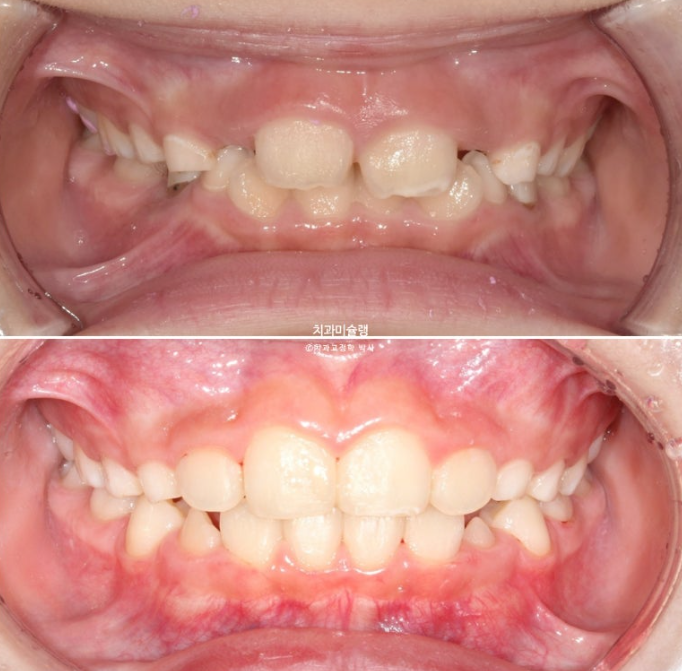

23년 10월, 교정치료를 위해 온 어린이 입니다.

앞니 두 개 높낮이 차이, 앞니가 깊게 물리는 과개교합이 보입니다.

앞니 네개 중 옆 앞니 즉 측절치가 나올 공간이 좁습니다.

아래도 마찬가지 입니다.

앞니가 벌써 삐뚤삐뚤 합니다.

송곳니가 나올때는 어떻게 될까요?

덧니 100% 예약입니다.

과개교합은 개선되었고 측절치 나올 공간을 악궁확장으로 미리 벌려줬기 때문에 측절치는 잘 내려왔습니다.

중심선은 잘 맞아졌고 과개교합은 더 개선이 되었습니다.

이제 전 후 비교 보겠습니다.

23.10~25.08